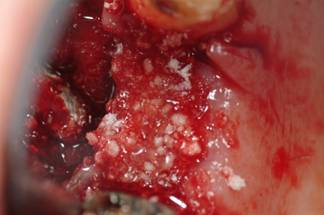

The remaining vertical bone defect was filled with a xenogenous bone graft (BIOSS®) (Fig 7), associated to an expanded polytetrafluoroethylene titanium-reinforced membrane (Gore-Tex ®).

Figure 7

Defect filling with xenologous bone.

A 3.0 silk detached suture was performed (Fig.8) and topic medication with povidone-iodine solution was applied. A systemic antibiotic prophylaxis with amoxicilline and clavulanic acid 1g was prescribed after 6 hours from surgery.

Figure 8

Sutured flap.